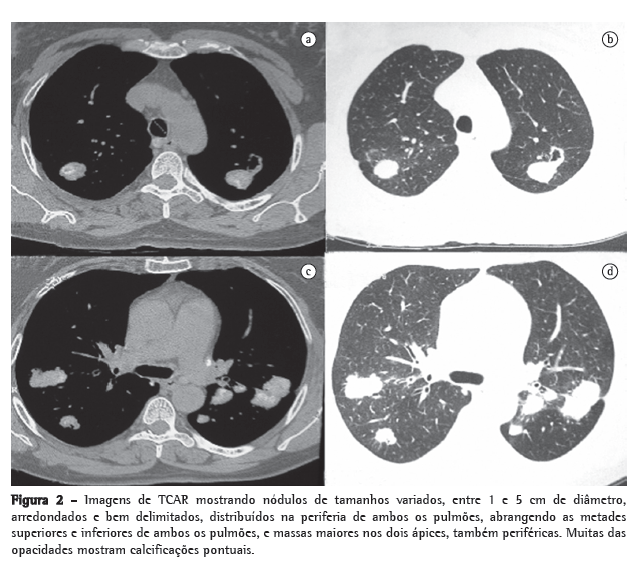

A TCAR do tórax revelou nódulos redondos bilaterais, bem delimitados, de distribuição periférica e, nos ápices, nódulos não maiores que 5 cm com as mesmas características. Muitas das opacidades mostravam calcificações pontuais. Pequenos nódulos centrolobulares, com atenuação em vidro fosco discreta, em regiões superiores de ambos os pulmões. Presença de adenopatia calcificada no mediastino (Figura 2).